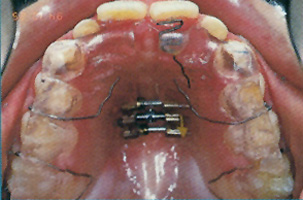

Ακίνητοι Μηχανισμοί - Ορθοδοντικός Δρ. Ζαρμπή

Πρόκειται για μηχανισμούς που συγκολλούνται στα δόντια και δε μπορούν να αφαιρεθούν από τον ασθενή. Απευθύνονται σε μετακινήσεις ακριβείας μεμονωμένων δοντιών κατά μήκος του άνω ή κάτω οδοντικού τόξου, ή οδοντικών ομάδων μεταξύ τους.

Αποτελούνται από πολλά διαφορετικά τμήματα που λειτουργούν ως ένα σύστημα το οποίο με περιοδικές ρυθμίσεις επιτυγχάνει τις επιθυμητές οδοντικές μετακινήσεις. Ακολουθεί ανάλυση των τμημάτων των ακίνητων μηχανισμών: